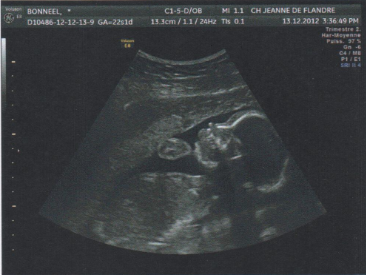

Nous avons eu confirmation lors de l’échographie du 2e trimestre le 13 décembre dernier, le p’tit virus est en fait une petite viruse 😀

Maxine sera donc parmi nous d’ici la fin avril, en attendant, elle mesure environ 25 cm et pèse 505g. Un joli paquet de pâtes comme dirait la gynéco 🙂

La voici en photo :

Tout va bien, tout est en place et fonctionnel, elle est parfaite!

Par contre elle est placée très bas, et déjà la tête en bas : ce que je prenais pour des coups de pieds dans la vessie sont en fait des coups de tête, une vraie headbangeuse 😀